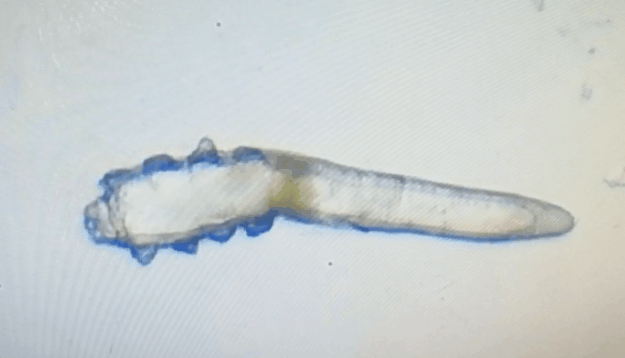

廈門眼科中心眼表及角膜病專家商旭敏博士指出:蠕形螨中的毛囊蠕形螨和皮脂蠕形螨可寄居于人體。在眼部,毛囊蠕形螨常寄居于睫毛囊,而皮脂蠕形螨多寄居于眼瞼皮膚的皮脂腺和瞼板腺。蠕形螨瞼緣炎是蠕形螨感染瞼緣所致的慢性炎性反應(yīng)性疾病,主要累及瞼緣皮膚、睫毛囊和腺體以及瞼板腺,以眼癢、眼異物感、眼干、瞼緣充血、鱗屑及睫毛根部袖套狀分泌物等為典型臨床表現(xiàn),嚴(yán)重者可引起結(jié)膜及角膜并發(fā)癥,該病可能具有一定的傳染性。

蠕形螨的危害不容小覷!?。?/strong>

蠕形螨會引起睫毛異常,引發(fā)瞼緣炎性反應(yīng),瞼板腺堵塞,引起結(jié)膜炎、角膜炎等并發(fā)癥,嚴(yán)重的話將發(fā)生角膜穿孔致視力損傷甚至失明。